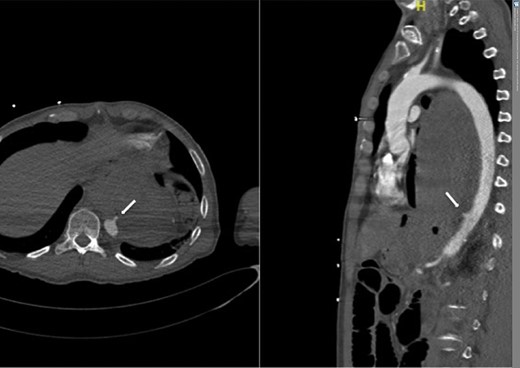

A 57-year-old male presented haemodynamically unstable with a blood pressure of 85/50 mmHg and a heart rate of 136 bpm with haematemesis, melaena and 4-day history of back pain. Fifteen years previously he was treated for a poorly differentiated adenocarcinoma (pT3 pN1 MX) close to the gastro-oesophageal junction with chemotherapy and trans-hiatal oesophagectomy. He received no radiotherapy. Apart from being a life-long smoker he had no other positive social risk factors or medical history. He underwent immediate oesophago-gastro-duodenoscopy (OGD). This showed fresh and clotted blood in the gastric remnant but no bleeding source was identified. He had a pulseless arrest during the OGD but underwent successful cardiopulmonary resuscitation. Following this a CT angiogram was performed. This demonstrated a fistula between the neo-oesphagus and the thoracic aorta (Fig. 1). Following discussion between an upper gastro-intestinal surgeon, a vascular surgeon and an interventional radiologist the patient was taken to the operating theatre. Under general anaesthesia an initial thoracic aortogram was performed from the right groin to confirm the presence and location of the AGF (Fig. 2). Following this, a covered thoracic stent graft (Cook Medical ZTA-24-105/diameter of 24 mm and length of 105 mm), was inserted via the femoral artery under image guidance. The stent graft, usually used in aneurysmal repair, was placed in the thoracic aorta across the fistula and occluded it. Subsequent angiogram showed no leak (Fig. 3). The patient became haemodynamically stable and had an uneventful recovery.

Angiogram prior to primary aortic stenting; leak via fistula demonstrated by arrow.